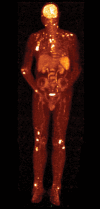

Patient concerns: A 76-year-old male of peculiar skin infection. Metagenomic Next Generation Sequencing and bacterial culture of skin secretions revealed M marseillense. To the best of our knowledge, we report the first patient diagnosed with disseminated M marseillense infection. Here, we identified only 8 other reports of patients with M marseillense infection.

Diagnoses: Disseminated M marseillense infection.